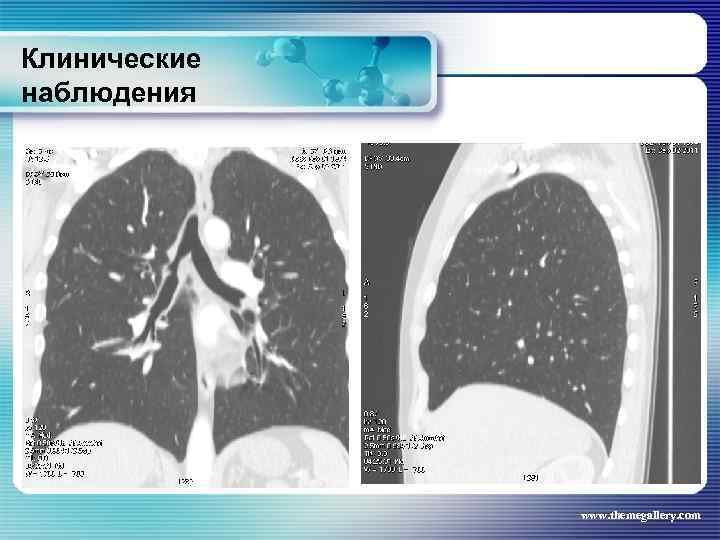

Клинические наблюдения Больной В. , 1974 г. р. Клинический диагноз: лимфома Ходжкина, нодулярный склероз IV В стадия с поражением подчелюстных, шейных, надключичных, подмышечных, паховых, абдоминальных, внутригрудных лимфатических узлов, легких, нижнегрудного и поясничного отделов позвоночника, костного мозга Проведено 8 циклов ВЕАСОРР, последний осложнился развитием тяжелого цитостатического пульмонита www. themegallery. com

Клинические наблюдения Больной В. , 1974 г. р. Клинический диагноз: лимфома Ходжкина, нодулярный склероз IV В стадия с поражением подчелюстных, шейных, надключичных, подмышечных, паховых, абдоминальных, внутригрудных лимфатических узлов, легких, нижнегрудного и поясничного отделов позвоночника, костного мозга Проведено 8 циклов ВЕАСОРР, последний осложнился развитием тяжелого цитостатического пульмонита www. themegallery. com